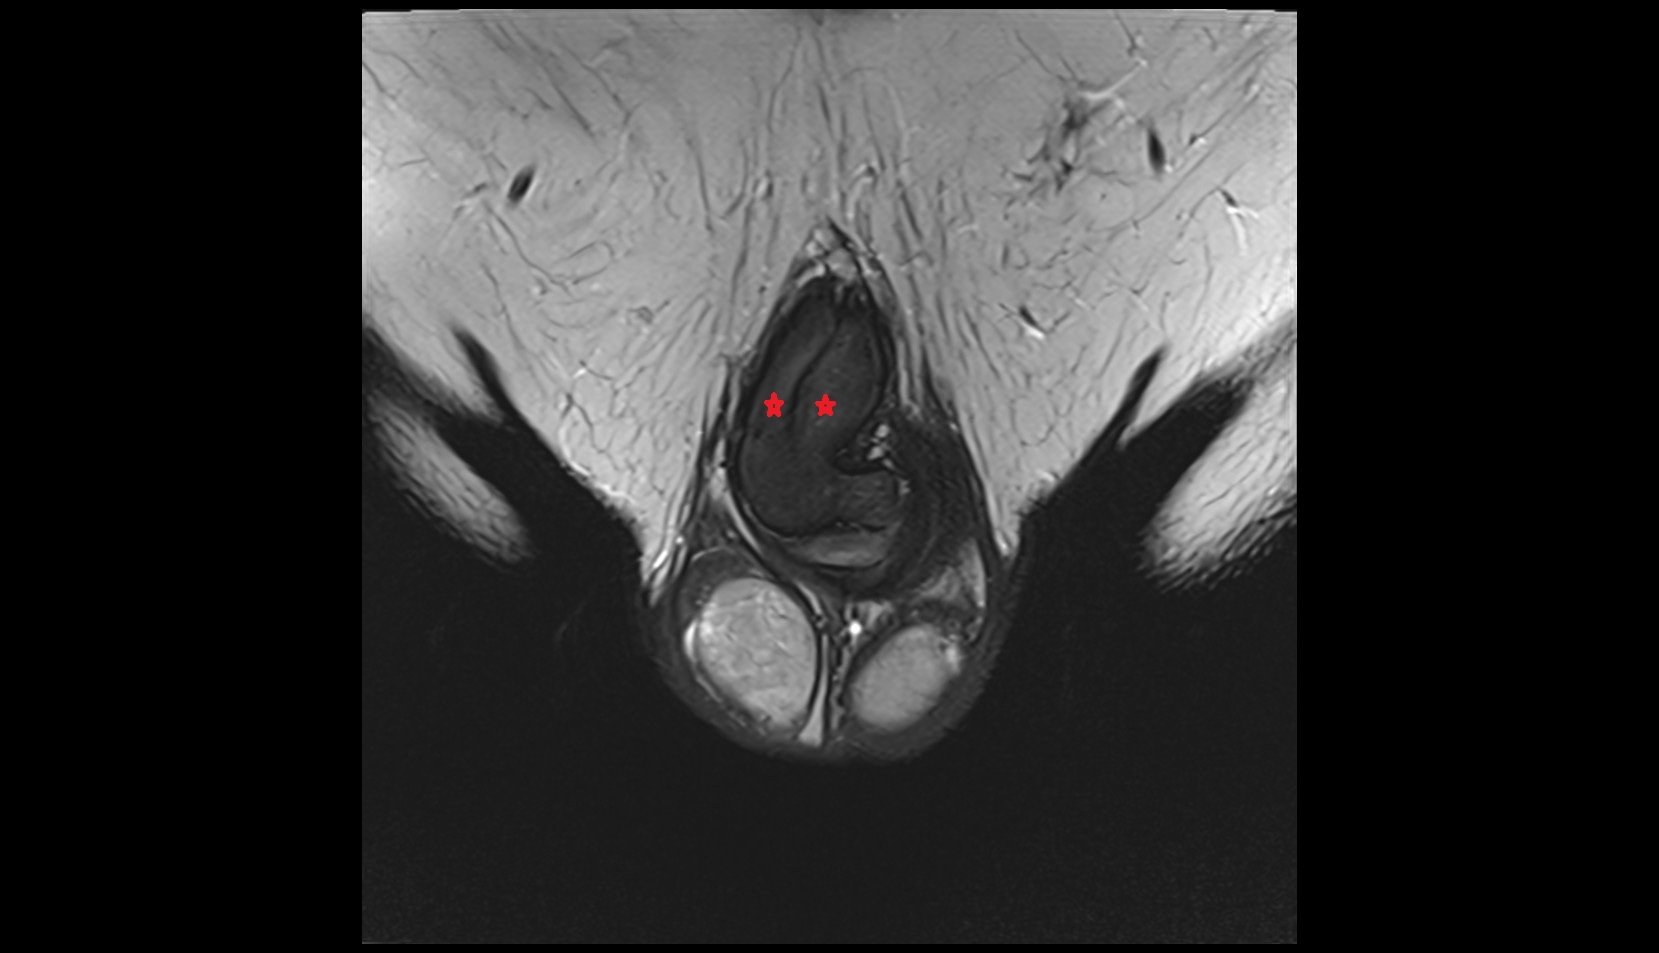

- Corpus cavernosum

- Corpus spongiosum

- Glans penis

- Corona of glans penis

- Testis

- Tunica albuginea (penis)

- Tunica albuginea of testis